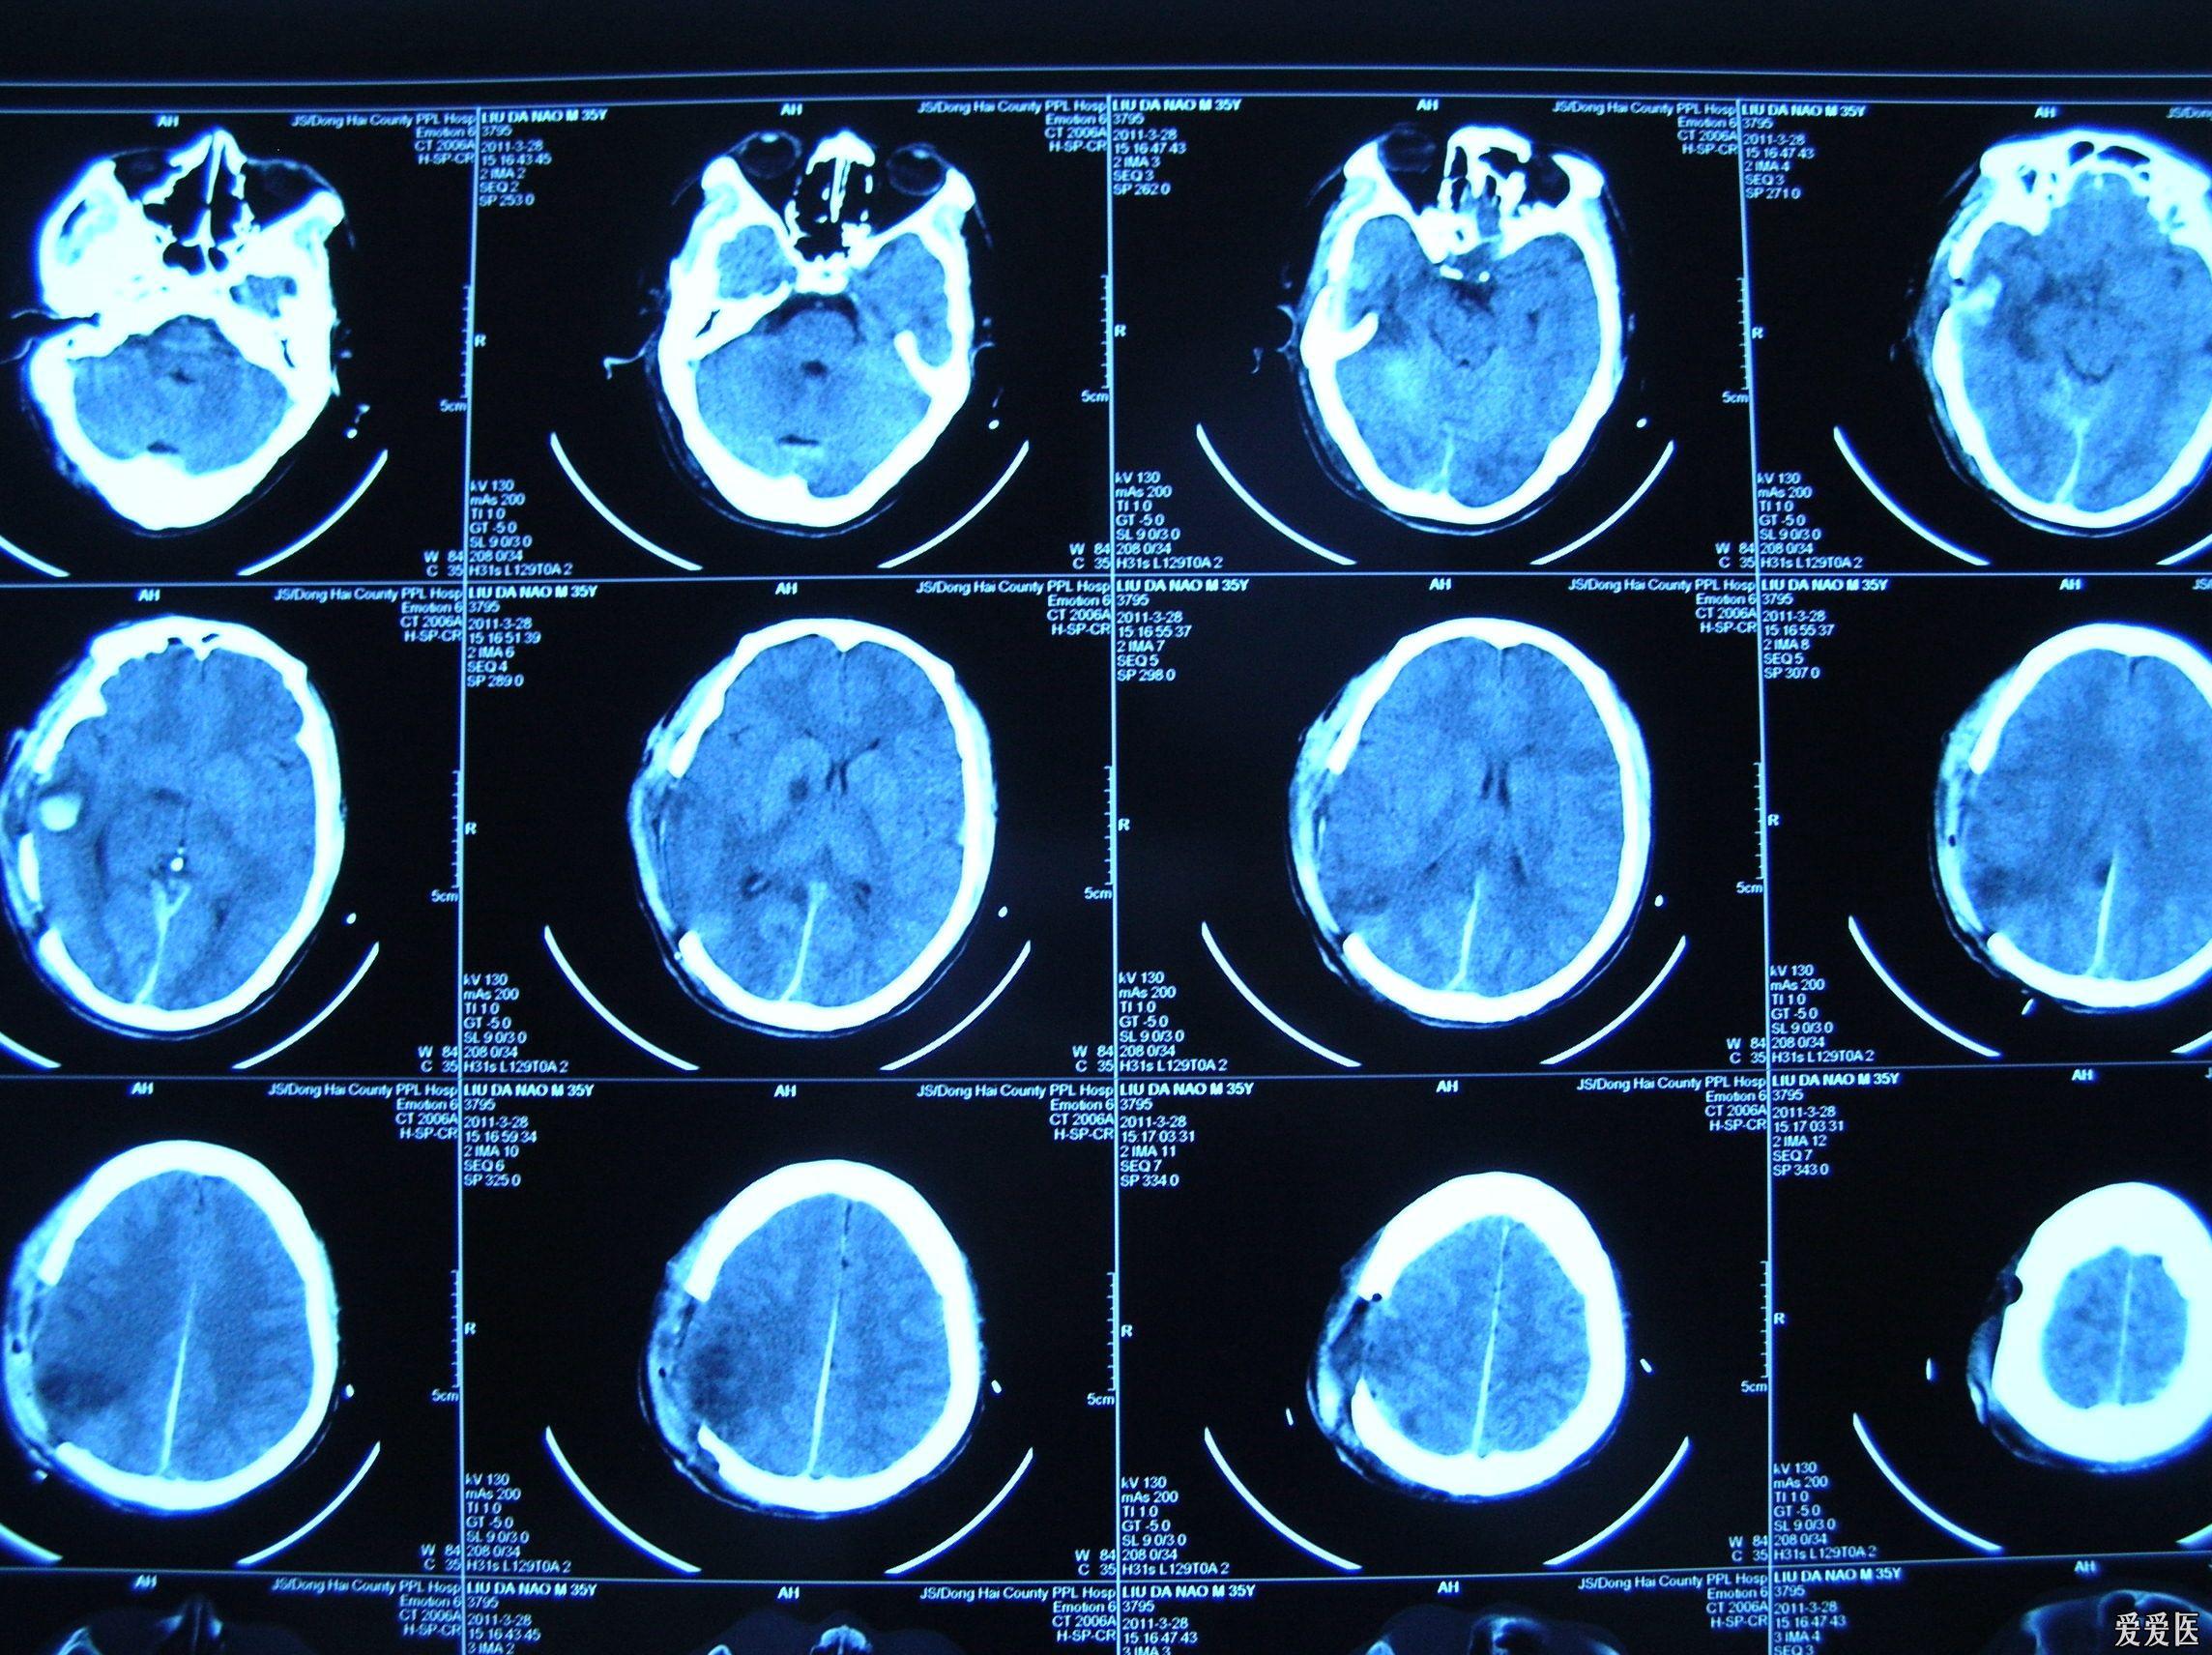

脑疝CT表现

解剖&影像|脑疝的5种分类及其经典的影像表现

脑疝,脑死亡丨影像及临床诊断要点